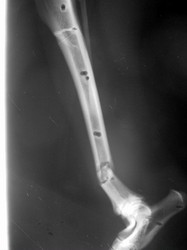

Fijación Externa

PRÁCTICAS CURSO DE FIJACIÓN EXTERNA PERFECCIONAMIENTO.

Híbrido.